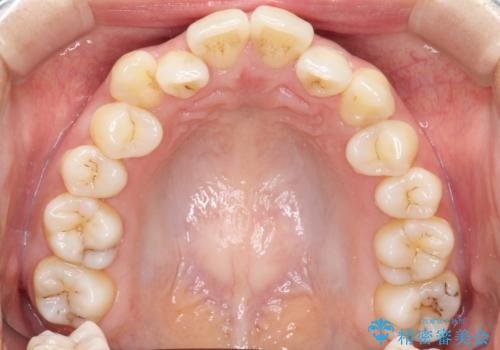

前歯が前後反対にかんでいる インビザラインによる目立たない矯正

- 前歯のかみ合わせを主訴に来院されました。

なるべく目立たずに矯正をしたいとのことで、インビザラインで矯正をすることとしました。

歯と歯の間をわずかに削り、ガタガタを改善しました。